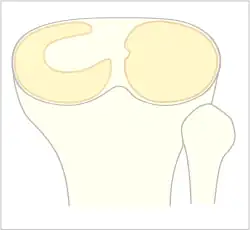

Zum besseren Verständnis des Krankheitsbilds Scheibenmeniskus trägt eine allgemein anerkannte Klassifikation der Variationen des lateralen Meniskus bei, die Watanabe-Klassifikation.[5] Scheibenmenisken des Typs 1 und 2 haben die gleiche Position innerhalb des Kniegelenkes wie normale Menisken, sind also an der Gelenkkapsel mit ihrer Basis verbunden. Nur ist ihre Form nicht dreieckig, sondern sie haben die Form einer kompletten oder inkompletten Scheibe, die aufgrund ihrer Position die beiden Gelenkoberflächen der beteiligten Knochen vollständig voneinander trennt – ähnlich einem Discus articularis, im englischen Sprachraum daher als discoid meniscus bezeichnet. Damit sind die Gelenkflächen prinzipiell sehr gut vor einem Knorpelverschleiß geschützt, solange der Scheibenmeniskus selbst keine Beschwerden auslöst. Typ-3-Scheibenmenisken (Wrisberg-Variante) sind im Wesentlichen nicht durch ihre Form oder Dicke, sondern durch ihre fehlende Fixierung an der hinteren Gelenkkapsel charakterisiert. Daher sind hier besonders häufig Schnapp-Phänomene zu erwarten.

Scheibenmenisken können einen unterschiedlich großen Bereich des Gelenkareals zwischen der Meniskusbasis und dem Zentrum des Gelenkes an der Eminentia intercondylica ausfüllen. Man spricht von kompletten (Typ 1) oder inkompletten Scheibenmenisken (Typ 2), wobei der Übergang von einem breiten normalen Meniskus und einem schmalen Scheibenmeniskus sich klar daran erkennen lässt, dass im Falle eines Scheibenmeniskus die Oberschenkelrolle in der Hauptbelastungszone bei arthroskopischer Beurteilung nicht die gegenüberliegende Gelenkfläche des Schienbeinkopf-Plateaus direkt erreicht.